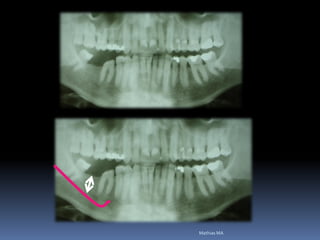

Exames Imaginológicos

Radiografias periapicais, telerradiografias e

panorâmicas;

Tomografias computadorizadas

Softwares de imagens 3D